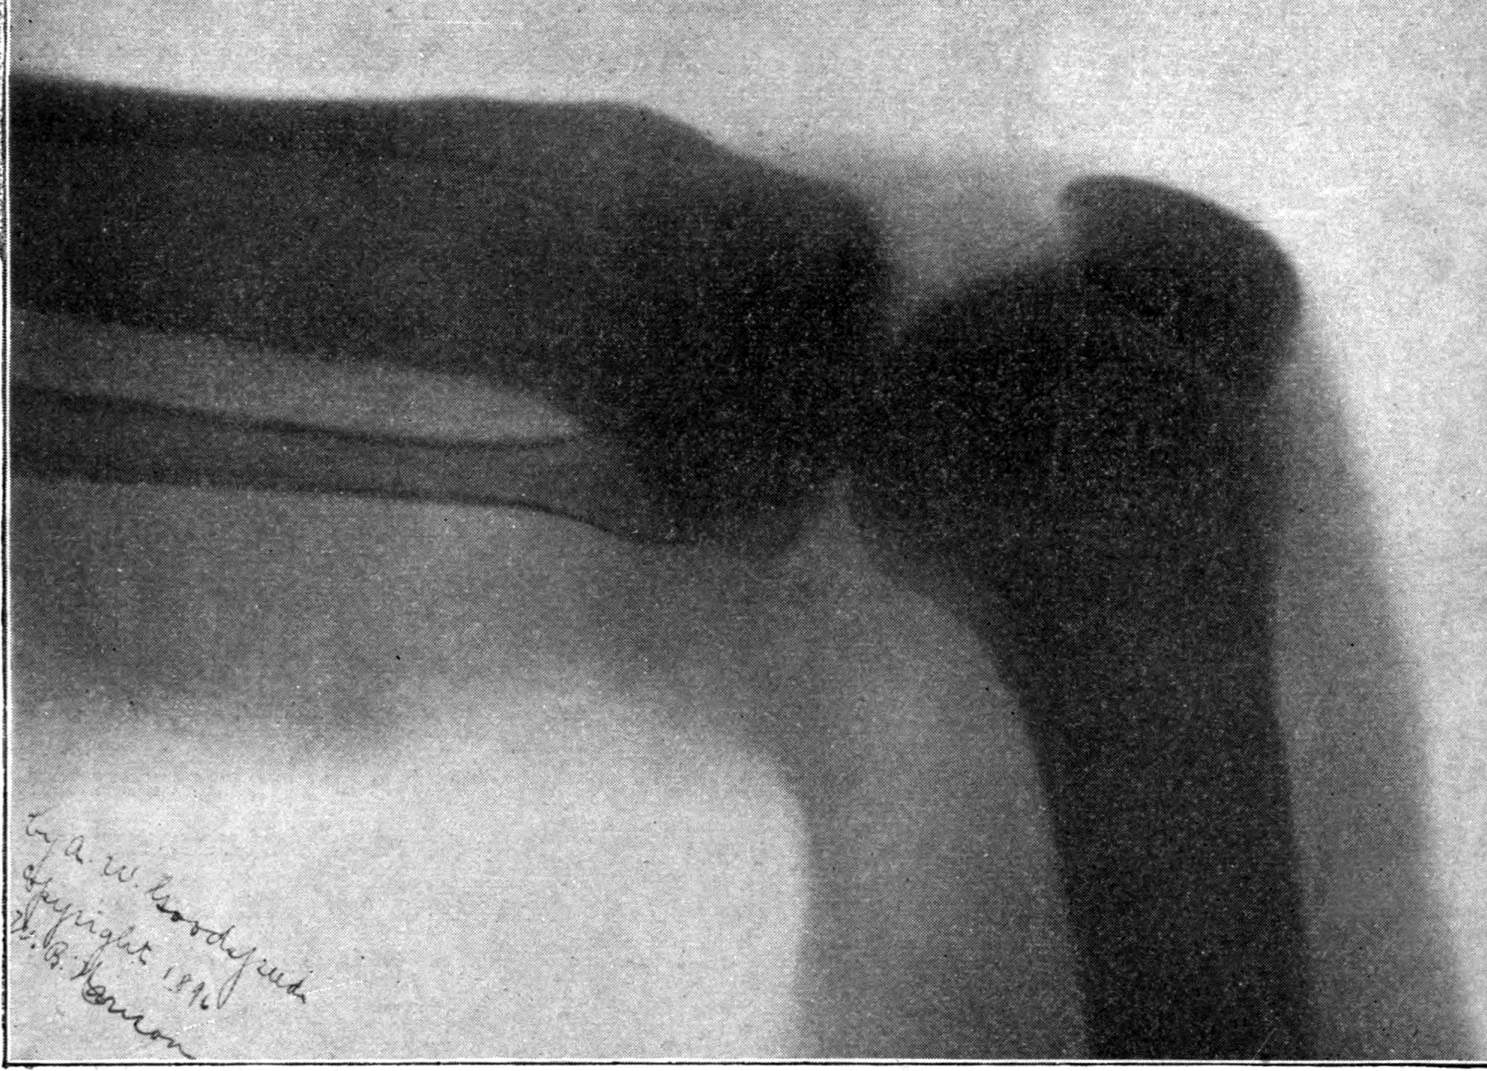

Fig. 4.—Knee, Knickerbocker Buttons, Bullet in Femur.

FROM SCIAGRAPHS BY PROF. DAYTON C. MILLER. § 204.